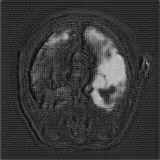

We obtain a subject-wise mean Dice score of 32.94% without any post-processing. By using a simple post-processing with erosion and dilation with filters, this number improves to 48.20% mean Dice score. In comparison, a similar study conducted by [3] consisting of a multitude of algorithms including AnoVAEGAN [4] and f-AnoGANS, obtained a best mean score of 27.8% Dice after post-processing by f-AnoGANS. Before post-processing the best method was Constrained AutoEncoder [8] with a score of 9.7% Dice. An exhaustive list is presented in Table 1. Figure 4 shows sample images of our results.

We obtain a subject-wise mean Dice score of 63.67% for the brain tumor segmentation. Utilizing a simple post-processing scheme of erosion and dilation with filter, we improve our mean Dice score to 68.01%. Figure 4 shows samples generated by our ASC-Net and Table 2 shows our before and after post-processing results. We attempted to apply f-AnoGANs [34] by following their online instructions and failed to generate good reconstructions as shown in Figure 5. The failure of AnoGANs in the reconstruction brings to light the issue with the regeneration based methods and the complexity and stability of GAN-based image reconstruction.